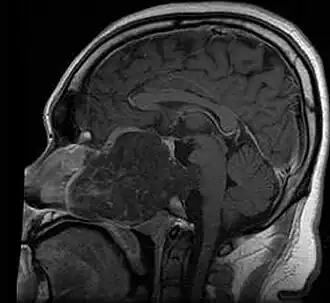

| MRI of extensive clival chordoma in 17-year-old male patient, axial view. Tumor in the nasopharynx extending from nasal cavity to brainstem posteriorly is clearly visible. | |

Chordomas can arise from bone in the skull base and anywhere along the spine. The two most common locations are cranially at the clivus and in the sacrum at the bottom of the spine.[2] Very rarely, chordomas present outside of the skull base or spine; these are called extra axial chordomas.[3]